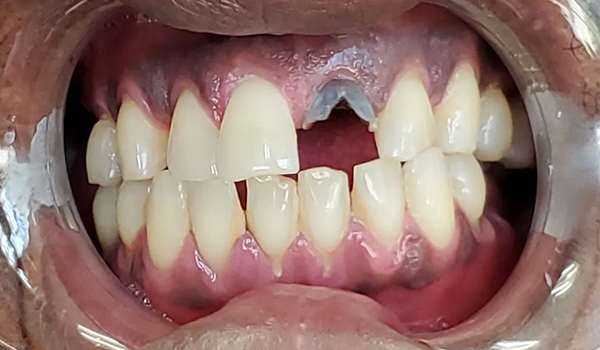

Before

After